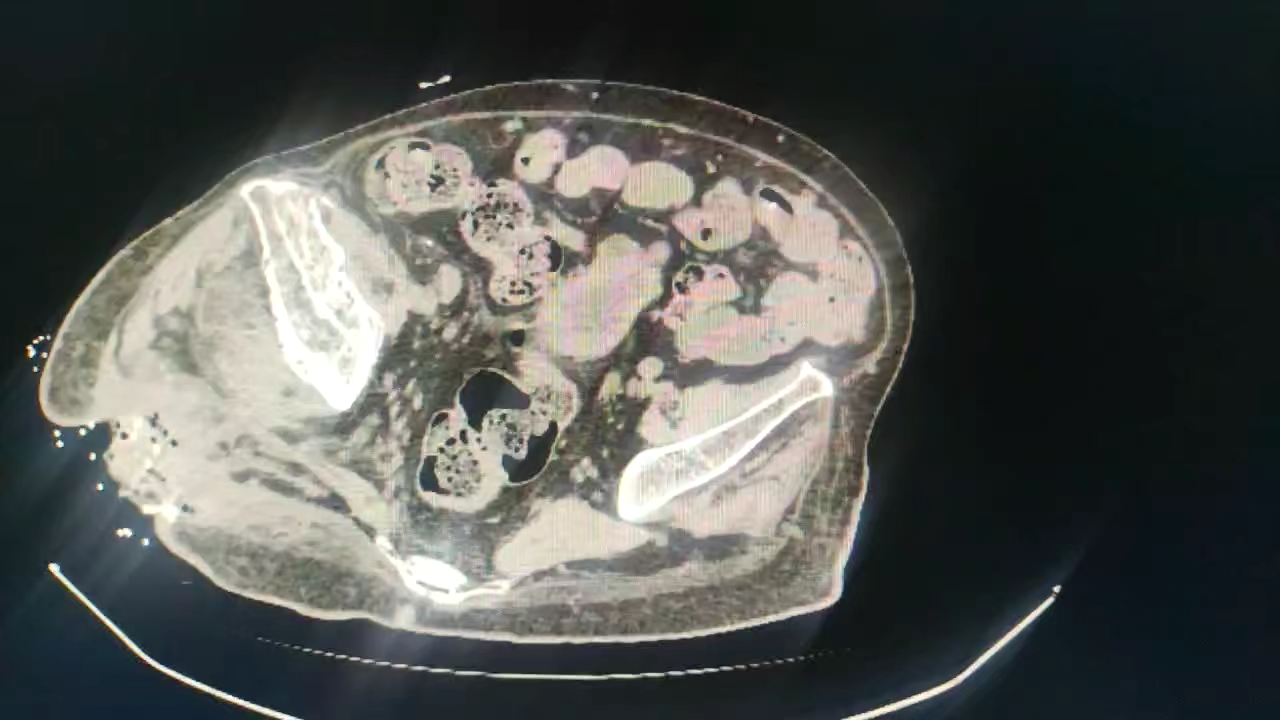

分享一例右股骨骨髓炎伴冠脉三支病变病例

初步诊断:1、右股骨骨髓炎(右髋部);2、截瘫;3、2型糖尿病;4、泌尿系感染;5、贫血;6、胸椎骨折术后;7、右股骨、胫骨骨折术后;8、冠心病(三支病变)。

下一步讨论准备术前准备,行右下肢截肢术。大家怎么分析?